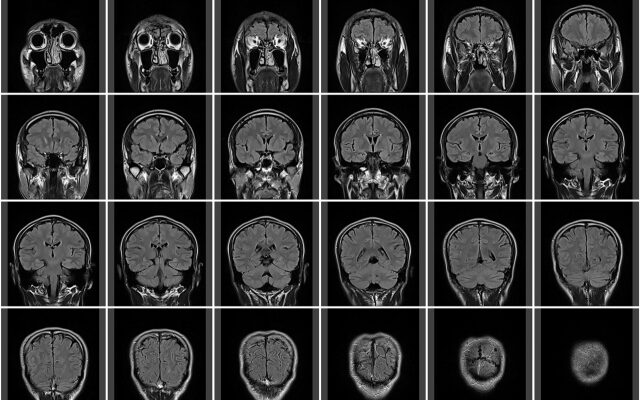

何と脳梗塞の跡を発見

年末の眼科の指示を受け、年が明けてから改めて設備のある病院でMRIを受けた。 病院で受付をして、最初に医師の問診があるのかと思いきや、先にMRIを受けてくださいとの指示で、指示通り検査室に向かう。 どうやらMRIは Continue Reading →